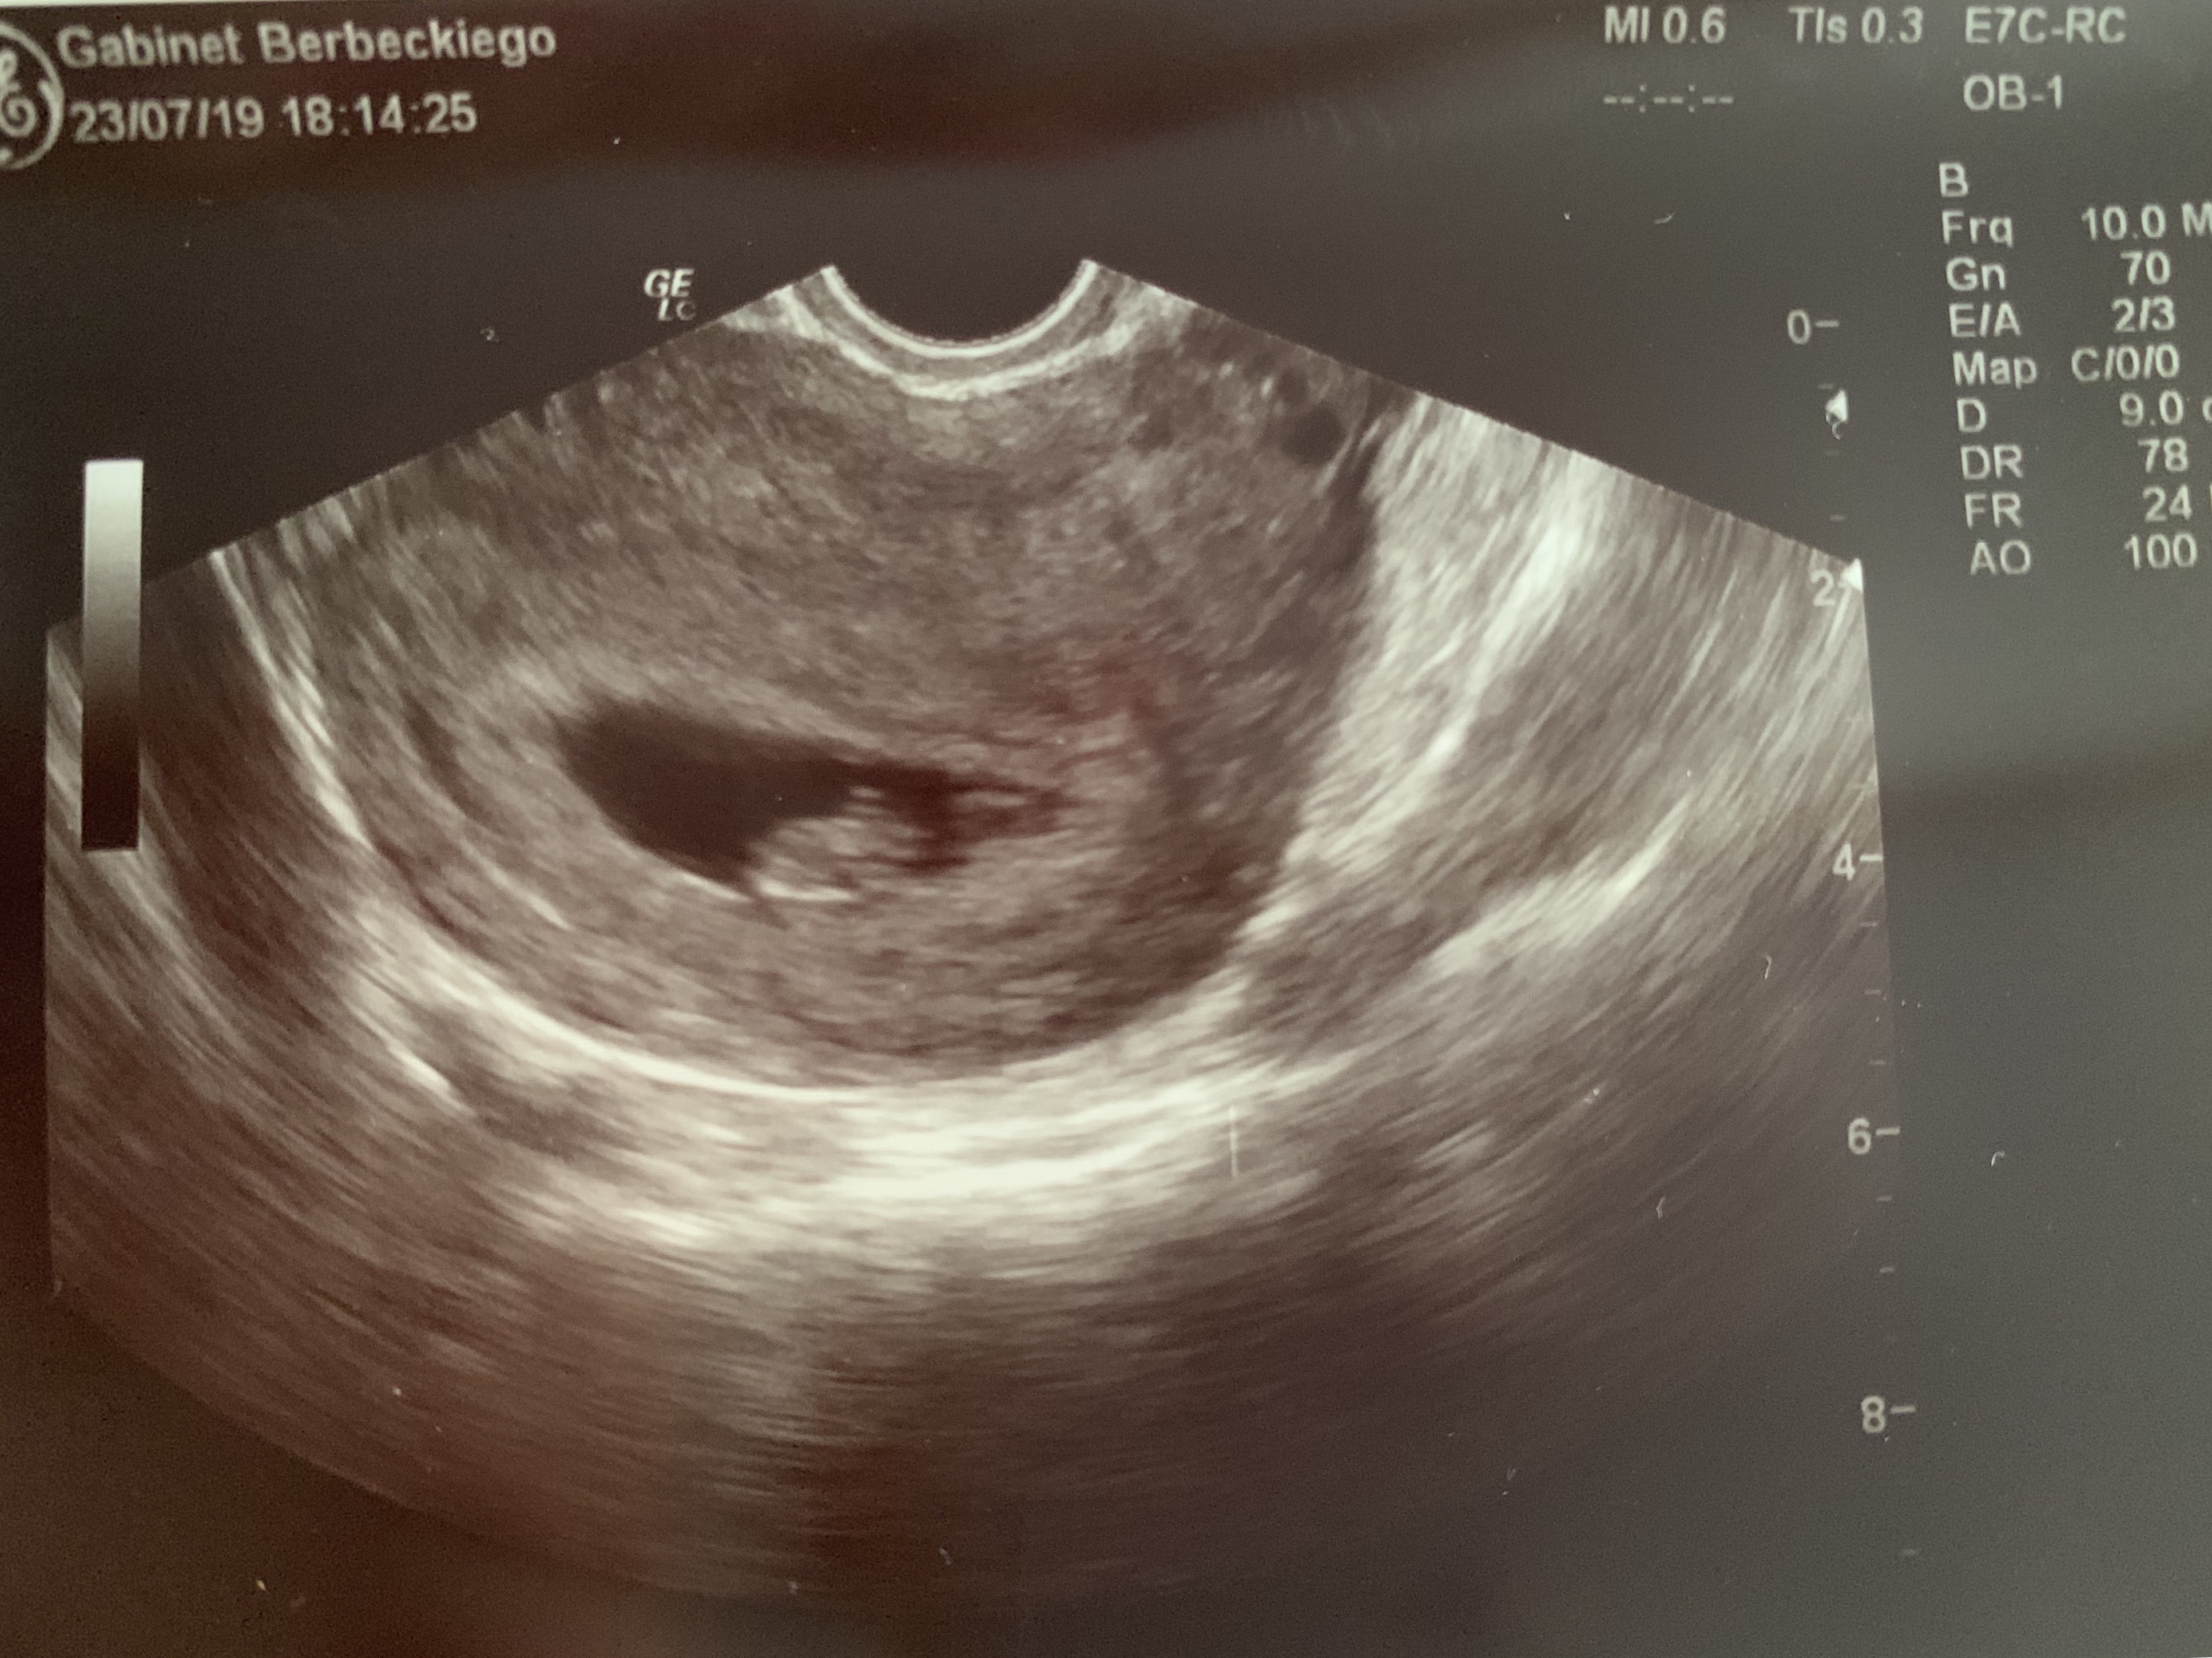

A słyszałeście o metodzie ramzi określania płci na podstawie zdjęć usg z 6-8tc? :D dla niektórych kolejna bujda ale mi daje kolejną nadzieję że tym razem dziolche ustrzelilismy [emoji12]

Potem na podstawie zdjęć z okolic 12 tc i położenia wyrostka niby niemal 100% można określić.

Teraz to juz nam metlik w glowie :) czy to zdjecie to lustrzane odbicie czy faktyczny obraz? Na moim usg wychodzi, ze dzidzia jest z lewej strony, ale przyjelam, ze to lustrzane odbicie czyli w rzeczywistosci jest z prawej.